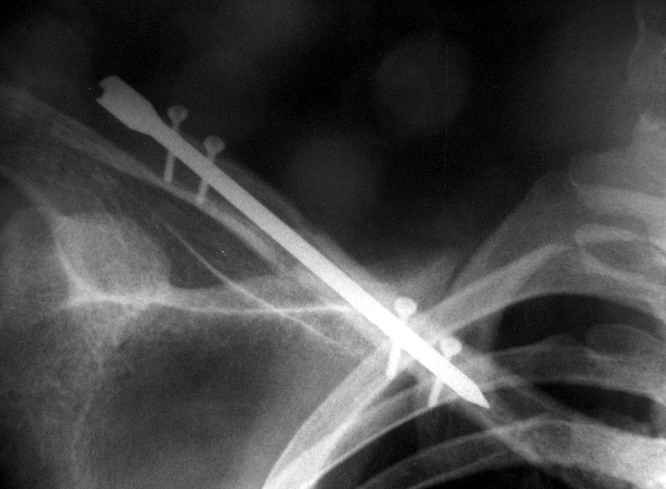

В приложении проект наших тезисов на съезд и клинический пример: Пациентка 23 лет поле неэффективного оперативного лечения (4 нед.) перелома ключицы спицей (была оперирована в С-Петербурге)(снимок после удаления спицы) и результат закрытого БИОС..

Существует, например, XS nail - фото в приложении, который запирается спицами 2 мм - не знаю, использовали ли его для ключицы, но почему бы и нет.